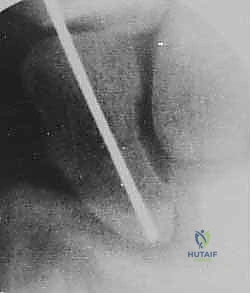

تقنية "التثبيت عن طريق الجلد" (Percutaneous Fixation) هي إجراء جراحي طفيف التوغل (Minimally Invasive). بدلاً من فتح الرسغ، يقوم الجراح بإجراء ثقب صغير جداً في الجلد (لا يتجاوز 3-5 مليمترات). من خلال هذا الثقب، وباستخدام جهاز الأشعة السينية المباشر في غرفة العمليات (C-arm Fluoroscopy)، يتم إدخال سلك توجيهي دقيق، ثم يتم إدخال مسمار خاص يسمى "مسمار ضغط بدون رأس" (Headless Compression Screw) مثل مسمار هيربرت (Herbert Screw).

الخطوة 2: تحديد مسار المسمار بدقة (Guidewire Placement)

هذه هي الخطوة الأكثر أهمية والتي تتطلب مهارة استثنائية. يقوم د. هطيف بعمل شق صغير جداً (بضعة مليمترات). باستخدام جهاز الأشعة، يقوم بإدخال سلك معدني